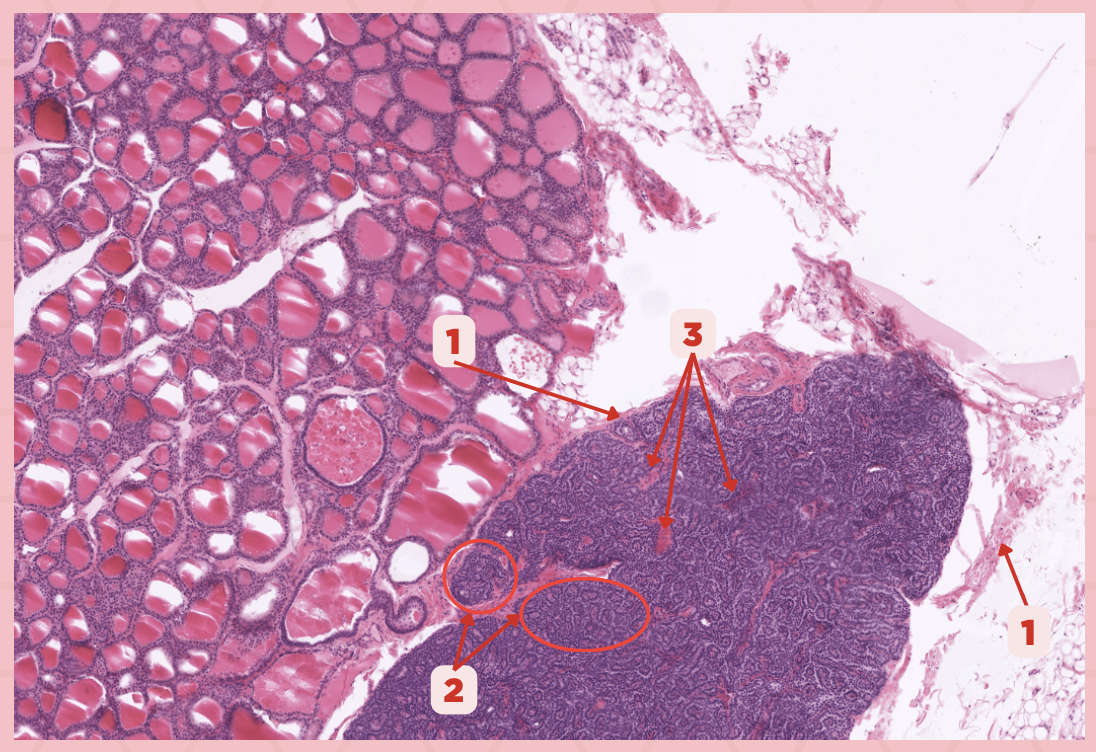

The parathyroid gland is divided into _____, packed with epithelial cells that form cords and clusters.

False

TRUE or FALSE. The parathyroid gland is only enveloped by its own thin connective tissue capsule.

Parathyroid Capsule

Identify the structure labeled as 1.

Lobules

Identify the structure labeled as 2.

Septa

Identify the structure labeled as 3.

Parathyroid

Identify the specimen.